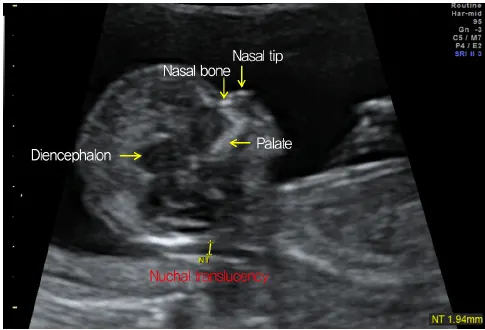

Child care begins at the fetal stage, and sophisticated fetal ultrasonography is used to track the health of an unborn child. We provide thorough evaluations and finely detailed photographs using the most recent technology to track your baby's growth and well-being.